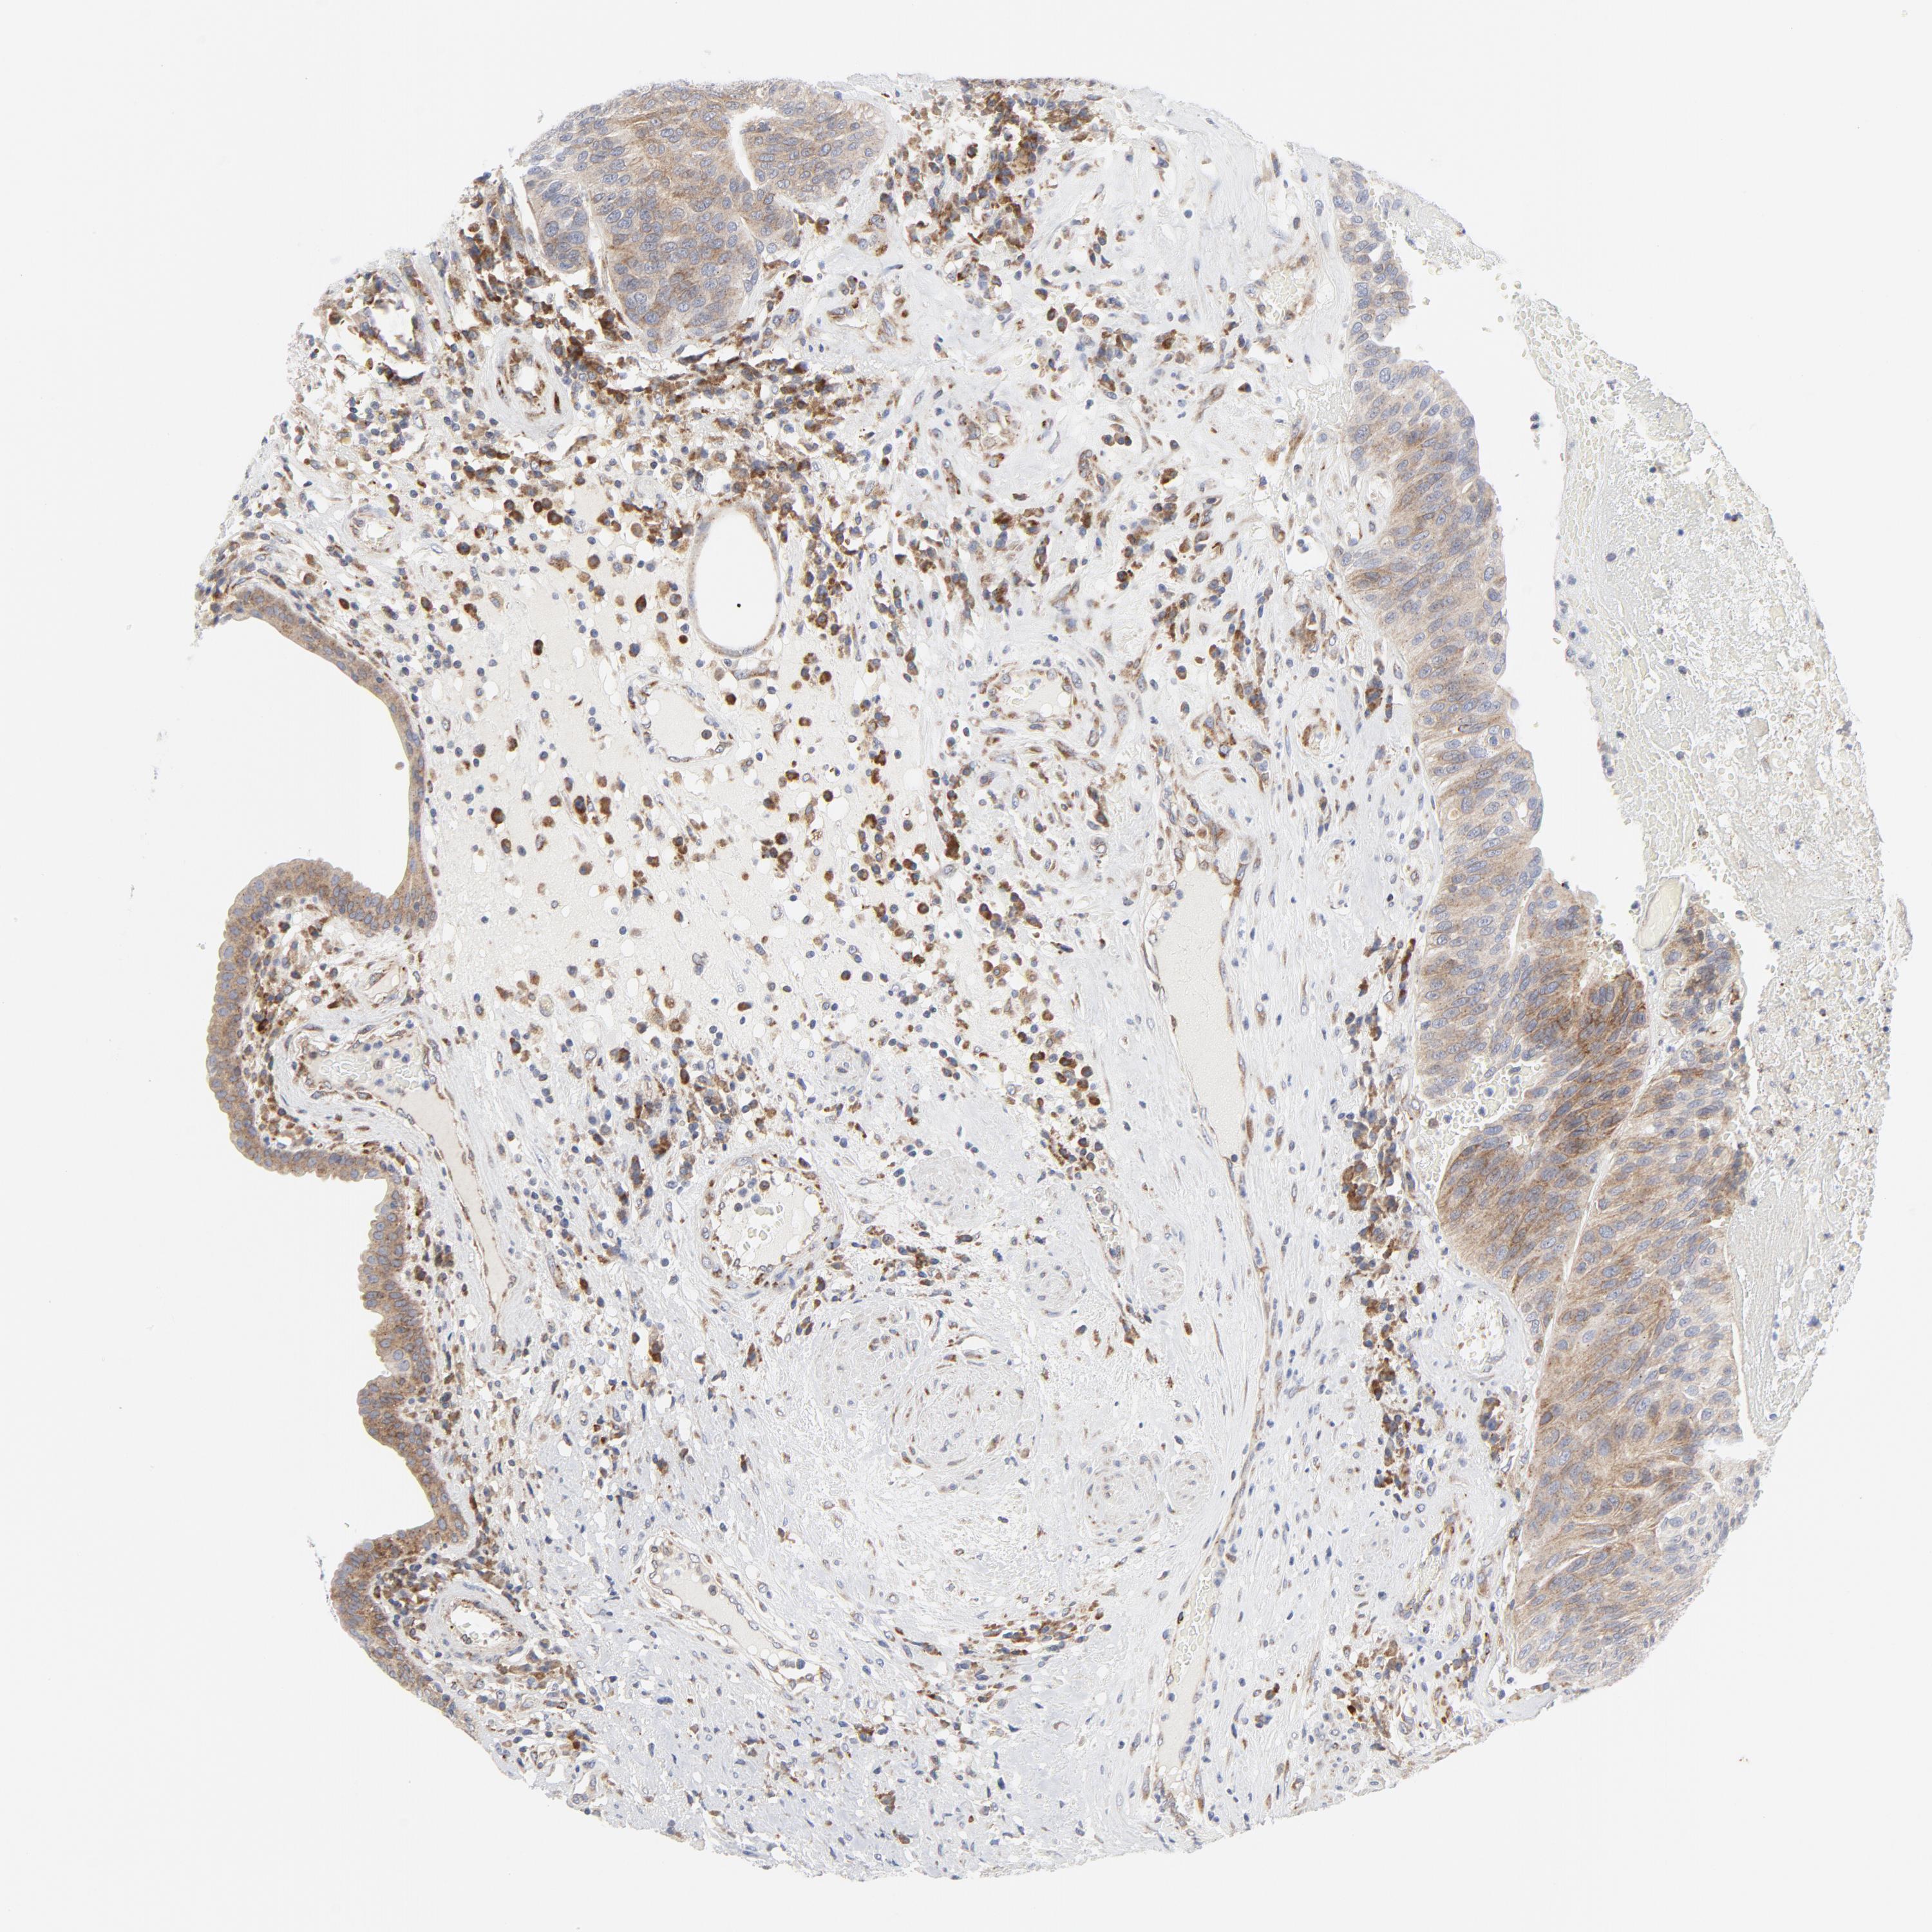

UROTHELIAL CANCER - Protein expressioni

A mouse-over function shows sample information and annotation data. Click on an image to view it in a full screen mode. Samples can be filtered based on level of antibody staining by selecting one or several of the following categories: high, medium, low and not detected. The assay and annotation is described here.

Antibody stainingi

Antibody staining in the annotated cell types in the current human tissue is reported as not detected, low, medium, or high, based on conventional immunohistochemistry profiling in selected tissues. This score is based on the combination of the staining intensity and fraction of stained cells.

Each image is clickable and will lead to virtual microscopy that enables deeper exploration of all samples and also displays staining intensity scores, fraction scores and subcellular localization as well as patient and tissue information for each sample.

Antibody HPA029925

Antibody CAB004490

Urothelial carcinoma, Low grade

Urothelial carcinoma, High grade